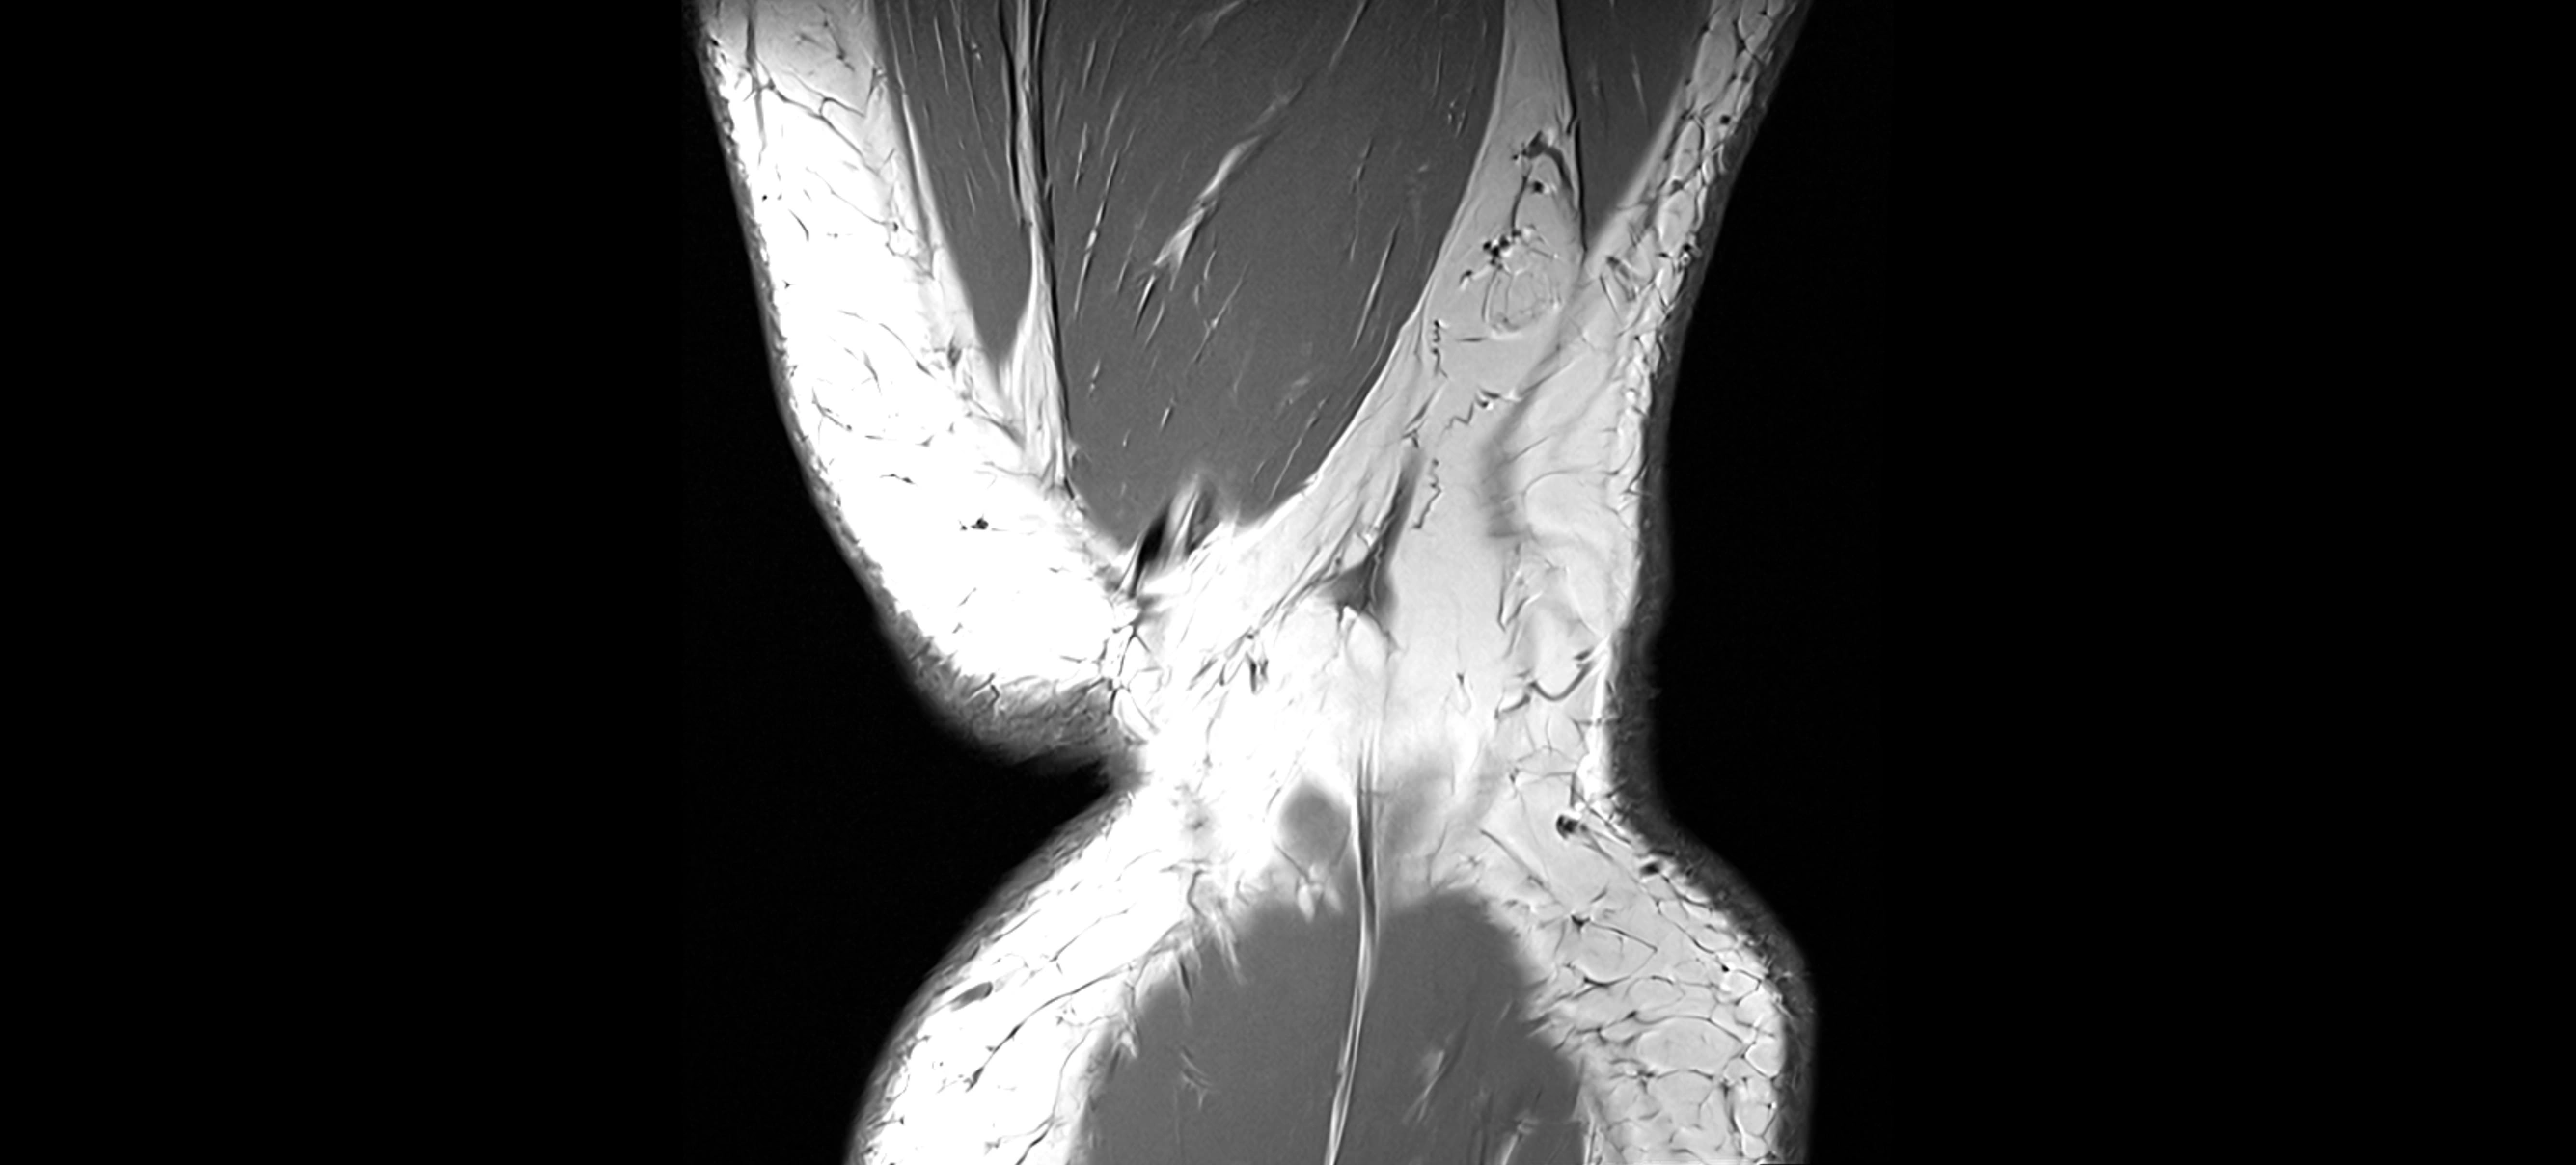

MRI images

image